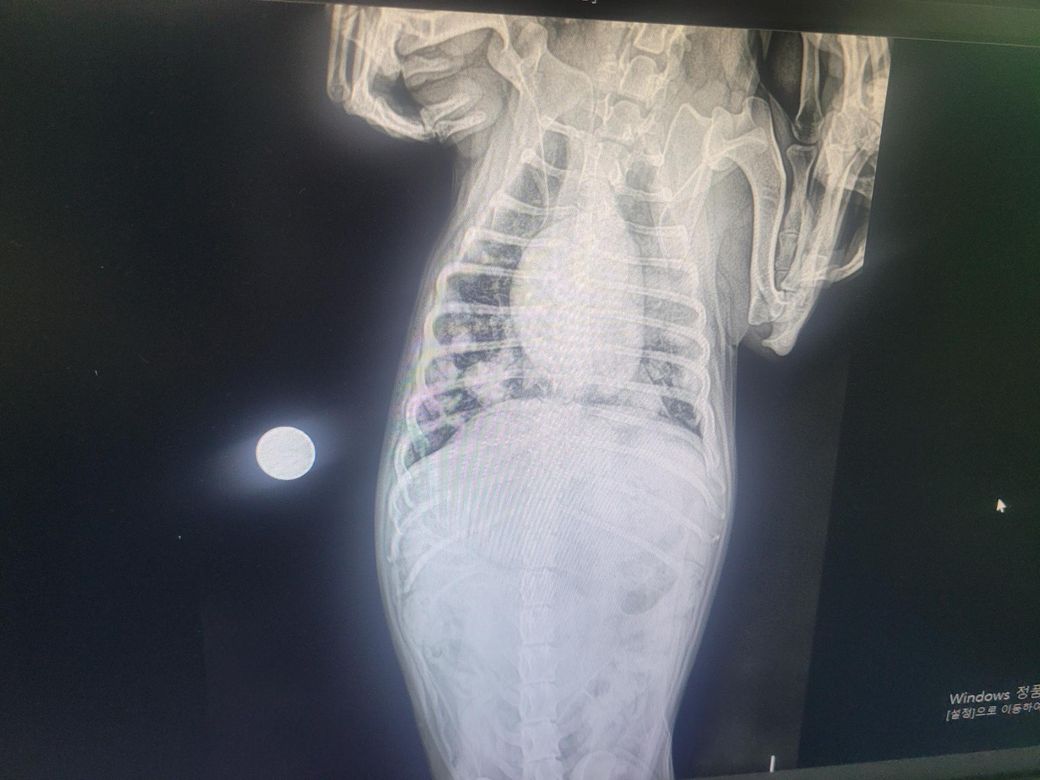

강아지 엑스레이 봐주세요 부탁드려요

구토는 이사하고 두달전부터 노란 구토가 시작되었구요 일주일전부터 설사도 같이합니다

체중이2키로 빠졌구요..

병원마다 진료내용이 다른데 봐주실수 있나요

보호자님께서 올려주신 영상을 확인했을 때, 의심되는 정황은 있습니다. 다만 엑스레이의 화질이 떨어져 정확한 판단이 어려운 점 감안해주시기 바라며, 정확한 판단은 항상 병원에 내원하셔서 수의사를 통해 이루어져야 합니다.

1. 흉부 방사선상 종양 전이 의심 상황

폐야에서 다발성으로 둥글고 경계가 비교적 뚜렷한 결절들이 보이는데, 이는 전형적으로 전이성 종양에서 흔히 관찰되는 형태입니다 (다른 장기에서 폐로 전이). 하지만, 드물게는 감염성 병변에서도 비슷한 양상이 보일 수 있어 확정적이지는 않습니다.

2. 간비대

복부 영상에서 간이 정상보다 커져 있는 모습이 의심됩니다. 간비대는 종양, 대사성 질환 등 다양한 원인에서 나타날 수 있습니다. 따라서 간비대 자체는 반드시 종양과만 연결되는 소견은 아니며, 추가적인 혈액검사와 초음파 정밀 평가가 필요합니다.

핵심적으로, 현재 영상 소견만으로는 종양성 질환 가능성이 높지만, 현재 엑스레이 사진으로는 폐로 종양이 전이되었을 가능성을 시사할 뿐, 추가적인 검사를 통한 확인이 필요합니다. 확정하려면 정밀검사가 필요하다는 점을 말씀드립니다.만 정확한 확인을 위해서는 혈액검사, CT 촬영 등이 필요할 것으로 보입니다. 다만 소형견으로 보이는 형태에, 체중이 2kg가 빠졌다면 만성 질환의 가능성이 크므로 빠른 시일 안에 정밀 검사를 추천드립니다.

사진 화질이 너무 나빠서 정확한 평가는 할 수 없으나 확실한것은 전이성 폐종양 가능성이 매우 높으니 CT 검사를 포함한 정확한 영상 검사를 추가로 받으시기 바랍니다. 보호자가 주춤하다가 환자를 빨리 죽이게 됩니다. 주춤하지 마시길,